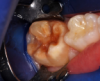

A 9-year-old boy had a partially erupted mandibular first molar with much hypocalcification of the occlusal surface and a large caries lesion involving the occlusal and buccal surfaces (Figure 1). The patient complained of continuing sensitivity to cold stimulus and air inspiration. Because the tooth was only partially erupted, consideration for stainless steel crown full coverage had to be delayed. As an interim repair, it was decided to debride the carious tooth substance and place a light-hardened calcium silicate/mineral trioxide aggregate (MTA) liner, followed by a bonded restoration. After inferior alveolar block anesthetic injection and cotton roll isolation, cavity outline form was cut using a high-speed, water-cooled, medium-grit cylindrical diamond bur (Figure 2). Insufficient eruption precluded use of a rubber dam. A large, round bur at slow speed was used to debride the carious enamel and dentin. The prepared surfaces were swabbed for two 60-second applications of a 5% glutaraldehyde/HEMA solution for desensitization and disinfection of the preparation.6,7 Cavity liner was then injected and spread over the deepest sections of the cavity floor and hardened with the visible light beam (Figure 3). After a self-etching bonding agent was applied over the remaining enamel surfaces, without the need for any type of matrix, an RMGI bioactive ionic resin-based composite was injected, in one portion, into the preparation and spread over the four cusps using a ball burnisher. This restorative complex was then photo-polymerized using two 20-second exposures of the visible light beam (1,200 mW/cm2). The restoration was trimmed and finished with large, round diamond burs at slow speed, and occlusion was evaluated with articulating paper and adjusted.

The repaired molar is shown immediately after treatment (Figure 4) and at 13 months (Figure 5). It was hoped that the restoration of the molar would last long enough that stainless steel crown full coverage would not be needed before precision cast crown placement late in the teen or adult years. However, stainless steel crown coverage could be considered, as needed, pending more eruption of the tooth.

Images of the repaired molar immediately after restoration

Figure 4

13 months postoperatively

Figure 5